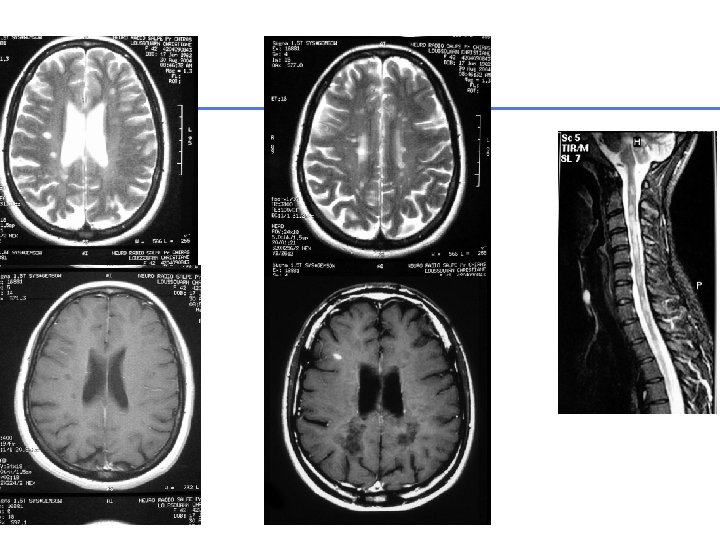

IRM encéphalique Pittock et al, 2006 Arch Neurol • N=60 patients • Durée de suivie: 6 ans +/- 5 • 36 anomalies cérébrales (60%)

2008 January 2010 32

• Après 3 ans d’évolution: – Ac anti-NMO + – Myélite cervicale

Nouveaux critères Wingerchuk et al, 2006, Neurology • Névrite optique • Myélite aigue • 2 critères sur 3: 1. IRM médullaire: 1 HS T 2 étendu ≥ 3 corps vertébraux 2. IRM cérébrale ne remplissant pas les critères de SEP 3. Ig. G anti-aquaporine 4 sensibilité 99%, spécificité 90%